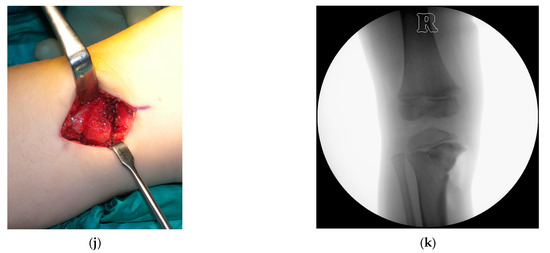

A fibular osteotomy was made in all cases by removing a 5 mm cylinder of bone through an incision of approximately 2–3 cm between the distal third and fourth fibula. Subsequently, a linear incision of 4–5 cm on the medial side of the tibia was made to subperiosteally expose the medial portion of the tibia. With the help of fluoroscopy, a chisel opening-wedge osteotomy was performed, aiming the tip of the chisel at the lateral margin of the tibial plateau. Desired valgus angular correction was achieved on the coronal plane and maintained by fitting a wedge of cancellous strut bone allograft, produced at the domestic Bone Tissue Bank (Figure 1). Each plane of tissue was then sutured, leaving the fascia open to avoid compartment syndrome. In some cases, drainage was maintained in the deep tissues for the next 24 h.

Figure 1. Case of a boy affected by bilateral ITV with intraoperative images of the surgical procedure on the right side: (a) clinical and (b) radiographic preoperative images at 3 years and 11 months of age; (c) clinical and (d) radiographic appearance at 10 years and 2 months of age (6 years and 3 months of follow-up) showed an optimal alignment of lower limbs; (e) draping of the right leg with the incision site marked on the skin; (f) medial side of the proximal tibia was subperiosteally exposed; (g) a 1.6 mm Kirschner wire was implanted aiming to the lateral border of the tibial plate and its position was checked under fluoroscopy; (h) an osteotomy was made with a chisel, avoiding a break through the physis, and (i) its position was checked with fluoroscopy; (j) final position of the bone graft and (k) its radiographic appearance.